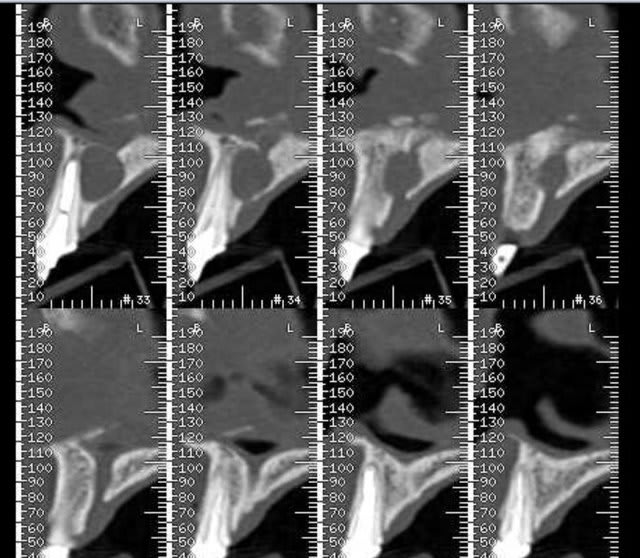

Voilà j'ai mieux que la gutta (pas de fistule visible en ce moment de toute façon )

Un scan. Voici quelques extraits.

Donc on extrait tout ce qui reste devant, on est d'accord ?

il semble y avoir une communication avec les sinus frontaux visible sur les coupes ,personnellement je serai très méfiant sur les extractions,que je déléguerais car les suites risques de ne pas être si simples, et ne les ferais pas sans avoir préalablement défini un plan de traitement post chirurgical surtout si le patient ne se plaint de rien actuellement;car ce type de situation mal anticipée peut amener des conflits.

J'ai pas prévu de réaliser cette chirurgie moi même heureusement. Le radiologue a en effet parlé au patient d'un possible commnunication (mais rien sur le compte rendu officiel bien sur).Si il y communication, celà posera t-il problème pour réaliser un comblement en vue d'un traitement implantaire ?